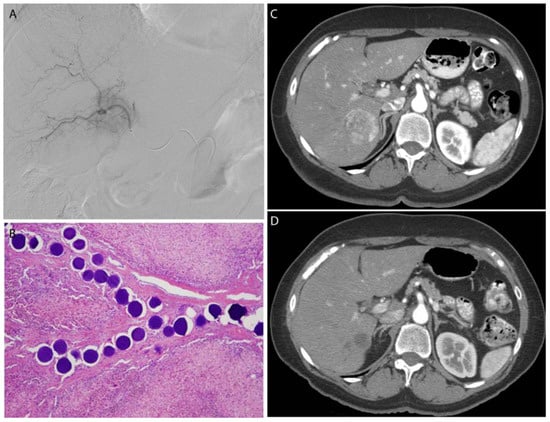

Figure 6.

A breast cancer metastasis to the liver was embolized with 100–300 μm, doxorubicin-eluting microspheres to reduce tumor size and vascularity prior to surgical resection. Selective catheterization (A) of the tumor was performed, with delivery of the microspheres within the blood vessels of the tumor (B). Post-procedure CT (D) demonstrates complete response of the tumor as indicated by fibrosis alone without any evidence of residual tumor compared to the pre-procedure CT (C).